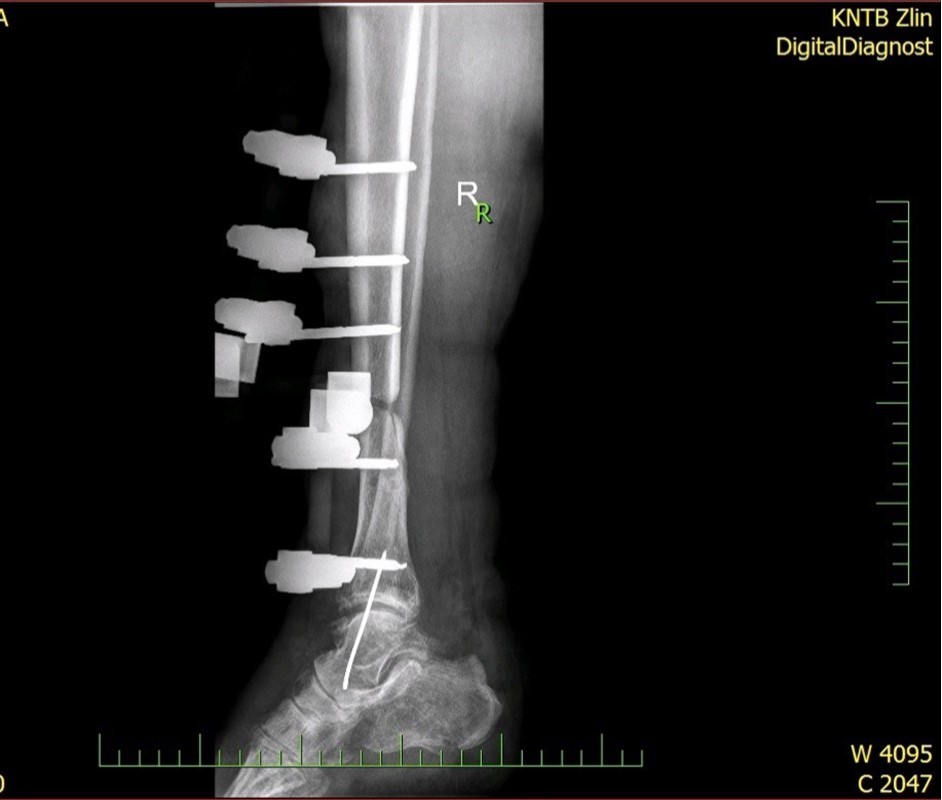

Figure 28.23 April. Surgery conversion of osteosynthesis. Removal external fixator and implantation intramedullary tibial nail. Gradual bone healing - last X-ray september 2019

Figure 29.23 April. Surgery conversion of osteosynthesis. Removal external fixator and implantation intramedullary tibial nail. Gradual bone healing - last X-ray september 2019